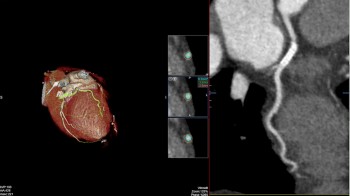

• MSCT koronarografija (prikaz krvnih žila srca CT-om, bez neugodnosti i komplikacija koje nosi klasična koronarografija), u saradnji s Poliklinkom dr.Al-Tawil